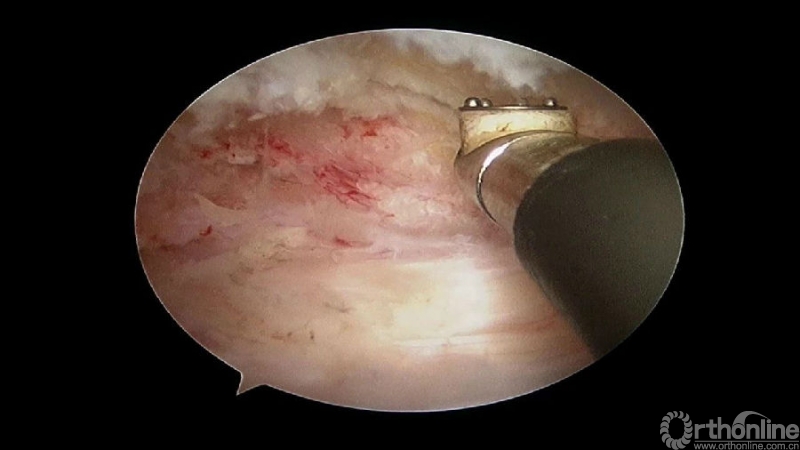

5. 减压完成后的止血非常重要,高效的止血方法有哪些?

(1)大头等离子刀头止血

(2)小头等离子刀头止血

(3)骨蜡

(4)明胶海绵